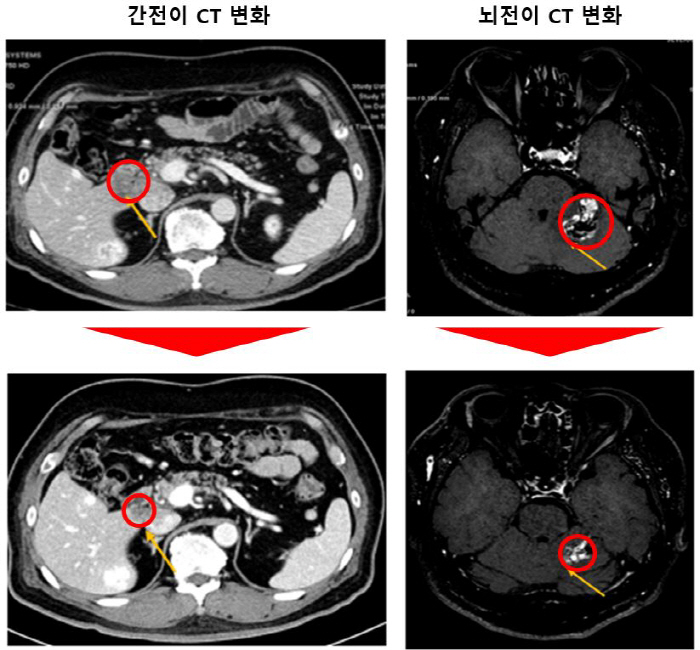

같은 연구팀이 동물을 대상으로 진행한 전임상 시험에서도 좋은 성적을 확인할 수 있었다. KRAS G12C 돌연변이 비소세포폐암 환자와 소토라십 치료를 받고 내성을 보이는 환자 종양을 마우스에 이식한 실험에서 우수한 효과를 나타냈다. 나아가 뇌전이까지 나타난 마우스도 뇌종양 감소를 보였다.